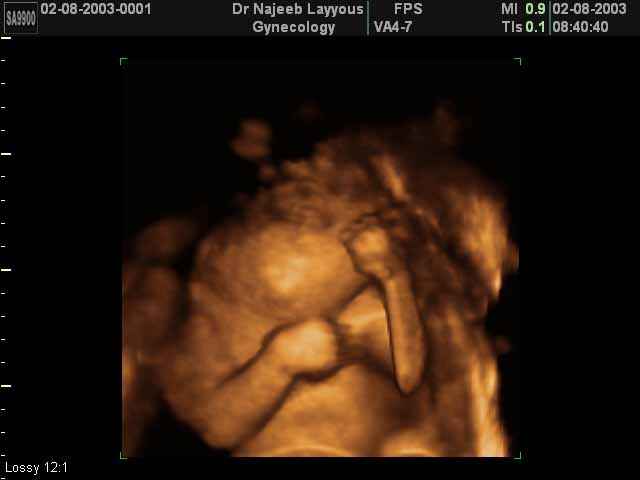

- Fetal Face Ultrasound Photos

- 3D Fetal Profile Ultrasound Scan Photos

- Fetal Parts Ultrasound Scan Photos

- 3D Fetal Limbs Ultrasound Scan Photos

- First Trimester Ultrasound Photos

- Fetal Behavior Ultrasound Photos

- Multiple Pregnancy Ultrasound Photos

- Second Trimester Ultrasound Photos

- The Clinical Advantages of 3D and 4D Ultrasound

- Definition and Features of Four Dimensional Ultrasound

- Uses of 4D Ultrasound scan